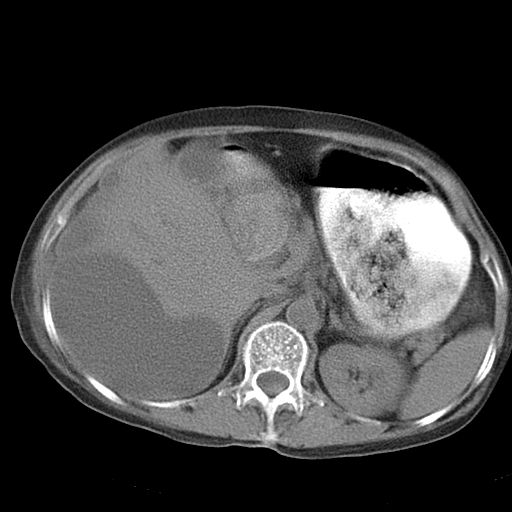

以下是引用dyqct在2006-12-7 21:08:00的发言:[br]考虑:1、肝内外胆管多发性结石伴肝左叶外侧段肝萎缩;[br] 2、右膈下多发脓肿;[br] 3、右侧少量胸腔积液、斜裂积液;[br] 4、左肾囊肿。

以下是引用jiazh在2006-12-7 20:37:00的发言:[br]肝脏周围半狐形低密度影,肝脏表面受压推移,考虑膈下脓肿可能性大;2、右侧胸腔积液

以下是引用拾荒者在2006-12-7 21:44:00的发言:[br]肝内外胆管多发结石,右膈下多发脓肿,右胸膜腔及叶间裂积液,左肾囊肿。[br] [br]